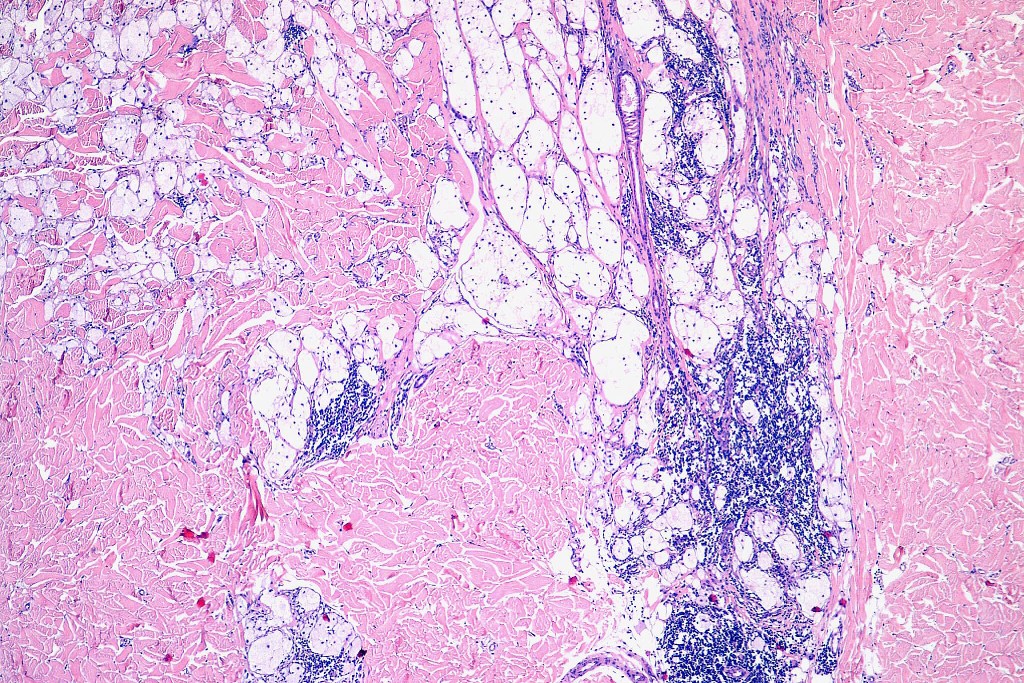

Histological features

•May affect the tumor in part or whole

•Enlarged cells with copious eosinophilic, foamy or clear cytoplasm (some authors include melanoma with clear cell change in the same category)

•Variable pigmentation

•Nuclei vesicular or hyperchromatic

•Pleomorphism is not generally marked and indeed can be very subtle

•Variable mitotic activity